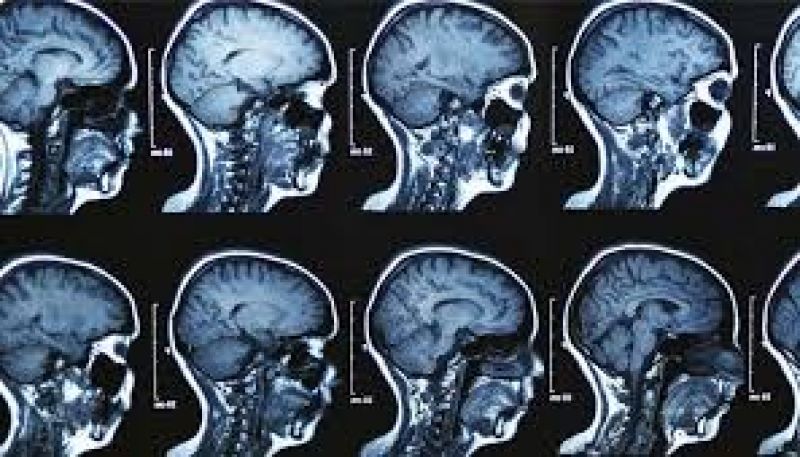

ਬ੍ਰੇਨ ਟਿਊਮਰ ਦਾ ਪਤਾ ਲਗਾਉਣ ਲਈ ਸੱਭ ਤੋਂ ਪਹਿਲਾਂ ਸਰੀਰਕ ਪ੍ਰੀਖਣ ਕੀਤਾ ਜਾਂਦਾ ਹੈ ਜਿਸ ਦੇ ਤਹਿਤ ਦਿਮਾਗੀ ਪ੍ਰਣਾਲੀ ਦਾ ਫੈਲਾਅ ਪ੍ਰੀਖਖ ਕੀਤਾ ਜਾਂਦਾ ਹੈ। ਡਾਕਟਰ ਇਹ ਦੇਖਣ ਲਈ ਇਕ ਪ੍ਰੀਖਣ ਕਰਦੇ ਹਨ ਕਿ ਕਰੈਨਿਅਲ ਨਰਵ ਠੀਕ ਹਨ ਜਾਂ ਨਹੀਂ। ਇਹੀ ਉਹ ਨਰਵ ਹਨ ਜੋ ਤੁਹਾਡੇ ਦਿਮਾਗ ਤੋਂ ਪੈਦਾ ਹੁੰਦੀਆਂ ਹਨ। ਸਰੀਰਕ ਪ੍ਰੀਖਣ ਤੋਂ ਬਾਅਦ ਰੋਗ ਦਾ ਪਤਾ ਚਲਦਾ ਹੈ। ਸੀਟੀ ਸਕੈਨ, ਐਮ.ਆਰ.ਆਈ, ਏਜੀਓਗ੍ਰਾਫ਼ੀ ਜਾਂ ਸਿਰ ਦੀ ਬਾਇਓਪਸੀ ਕੀਤੀ ਜਾ ਸਕਦੀ ਹੈ।